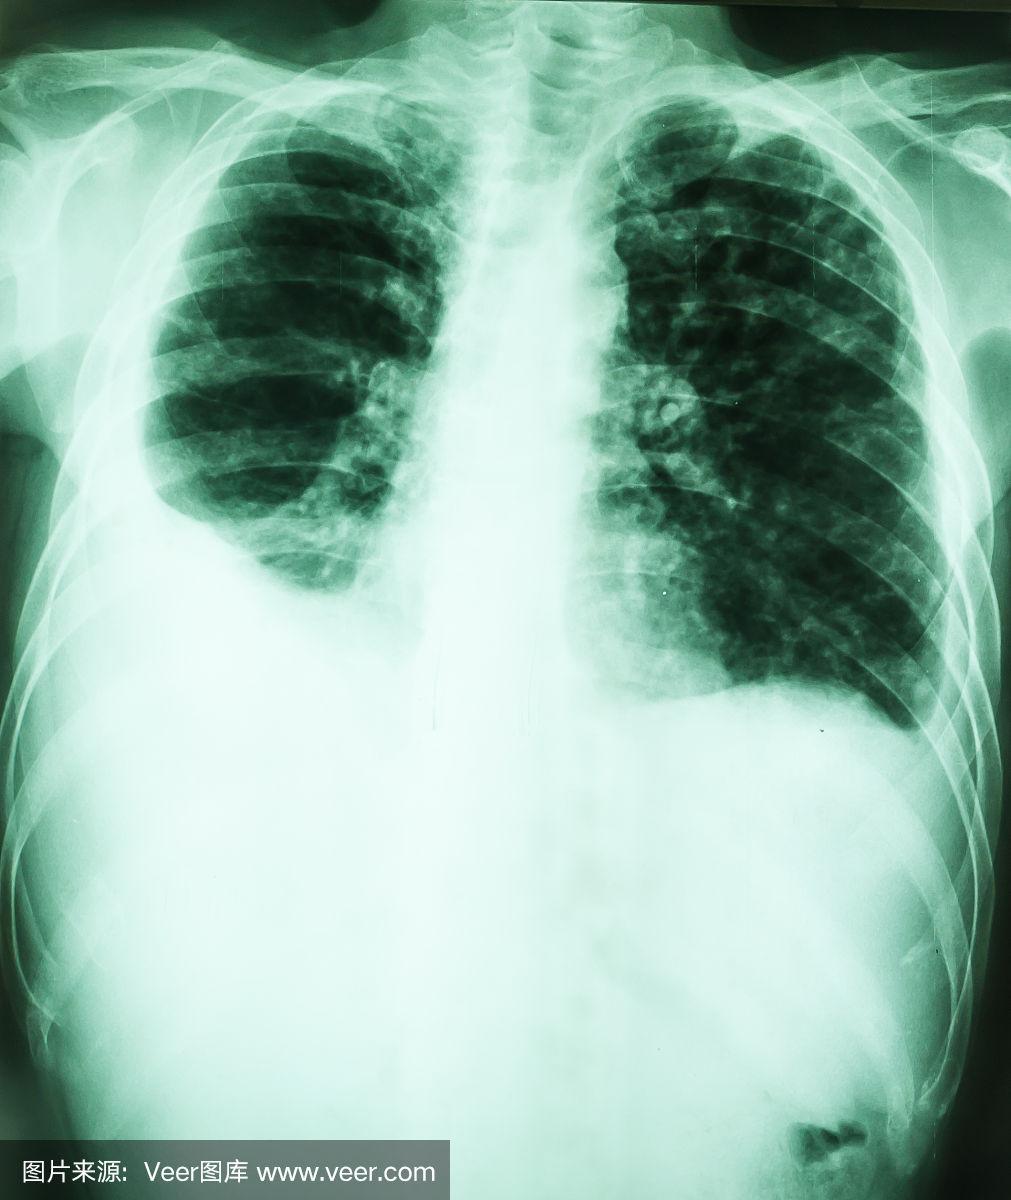

胸腔积液